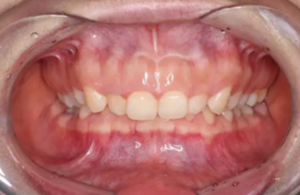

但前牙閉鎖合是上前牙下垂伸長(zhǎng),內(nèi)扣完全鎖住了下切牙,正面觀時(shí)我們??床坏较虑醒溃虑醒绖t常擁擠伸長(zhǎng)咬到了上腭內(nèi)的牙齦上,上下前牙發(fā)生的交角幾近180°。

前牙正常覆合

前牙閉鎖合-深覆合

前牙正常覆蓋

前牙閉鎖合覆蓋